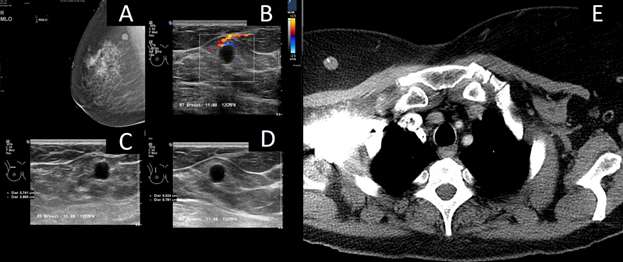

Breast metastasis from biopsy-proven ovarian carcinoma:

Figure 1: (A-C) Mammogram images demonstrate skin thickening on CC, ML and MLO view respectively. (D-G) Ultrasound demonstrates a vague hypoechoic area. There is associated diffuse left breast edema and skin thickening. (H) CT scan of the chest demonstrates asymmetric skin thickening of the breast. This is an unusual presentation of a hematogenous metastatic disease.